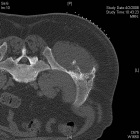

54 year old male with two year history of increasing swelling in left flank

Zoom image: Radiological image Radiological image.